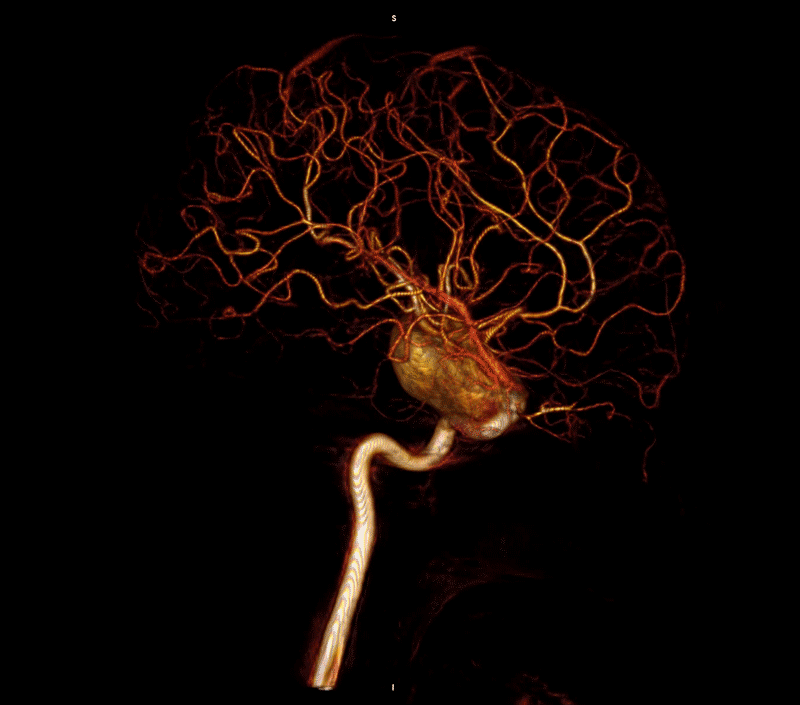

Parc Taulí has performed the repair of a giant aneurysm in a pediatric patient using the telescopic endovascular technique with two flow diverting stents. This minimally invasive intervention had already been done in adult patients; but it is the first time it is done with a pediatric patient in Catalonia.

This intervention was performed on a 15-year-old patient who came to Parc Taulí for an occasional headache. During the scan it was observed that he had a giant aneurysm of 4.5 cm in the internal carotid artery. After the multidisciplinary assessment with the specialists of the department of pediatric and adult neurosurgery and neuropediatrics, it was decided to perform a minimally invasive intervention using the telescopic technique, with two flow diverter stents, to avoid having to go through a surgical process.

During the intervention, which lasted one hour and thirty minutes, a selective catheterization was performed to reconstruct the arterial wall. To be able to do this process, microcatheters were inserted through the artery to be able to join the two healthy parts of the blood vessel and to be able to deploy the stents, creating a bridge. As the aneurysm was huge and very long, the telescopic technique was used.